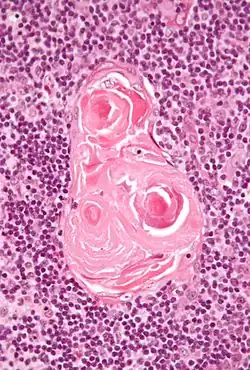

Тельца Гассаля

Тельца Гассаля (тельца вилочковой железы, "эпителиальные жемчужины") — слоистые эпителиальные тельца, расположенные в средней части мозгового вещества долек тимуса, образованы концентрически наслоёнными, плотными, сильно уплощёнными эпителиальными клетками. Диаметр до 50 мкм. Наибольшая концентрация наблюдается в 15 лет, затем резко убывает, но образование новых телец продолжается[1]. Название дано по имени английского врача А. Гассаля (1817—1894).

Тельца Гассаля состоят из эозинофильных эпителиальных ретикулярных клеток 6 типа. Функция телец Гассаля окончательно не установлена, но ряд данных свидетельствует об их роли в созревании дендритных клеток, участвующих в дифференцировке регуляторных Т-лимфоцитов.

В состав телец Гассаля входит два типа эпителиальных и семь типов вспомогательных клеток, которые на разных стадиях развития телец отличаются по ряду качественных и количественных признаков. Вспомогательные клетки активно взаимодействуют как между собой, так и с эпителиальными клетками обоих типов, влияя на развитие, функционирование и разрушение телец Гассаля. На основании полученных данных о развитии телец, нами предложен вариант их классификации, в основе которого лежат морфологические критерии и который отражает функциональные характеристики отдельных стадий развития телец. Основными клетками, формирующими тельца Гассаля, являются эпителиальные клетки мозгового вещества тимуса двух типов, которые отличаются друг от друга происхождением, строением и функциями.

Эпителиальные клетки I типа представляют собой субпопуляцию эпителиоцитов телец Гассаля, развивающихся из эпителиальных K14–К8+ клеток мозгового вещества. Они характеризуются округлой формой, синтезируют аутоантигены и подвергаются аутофагической гибели. Клетки II типа представлены субпопуляцией эпителиоцитов телец Гассаля, развивающихся из эпителиальных K14+К8– клеток мозгового вещества. Они характеризуются уплощенной формой, накапливают высокомолекулярные цитокератины и погибают в результате терминальной дифференцировки.